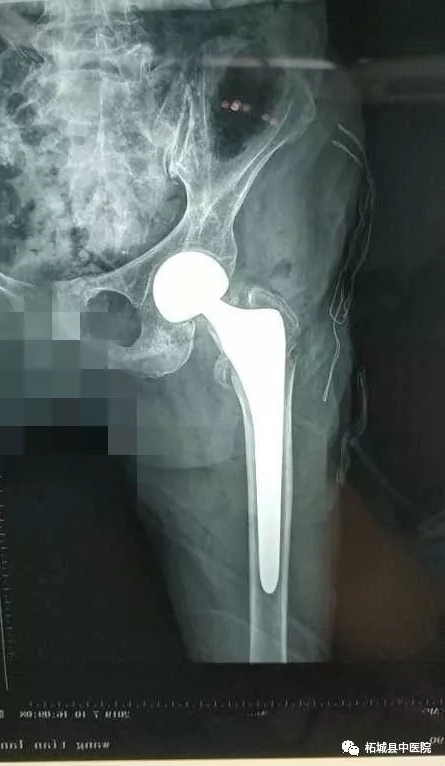

7月10日下午,在中医院北关院区百级层流净化手术室,殷晓东院长带领骨二科医师团队亲自手术,麻醉师张文选全程监控,内科专家王因仲、孙全立随时待命。仅耗时20分钟就顺利地完成了主操作。当老人被平安送出手术室的一刻,柘城中医院乃至柘城县 高龄髋关节置换手术患者的纪录也再次被刷新。

为了表达对老人家的祝福,减轻老人家庭负担,让老人安心养病,医院特减免老人手术费及部分材料费,祝“老福星”早日康复,安享晚年!